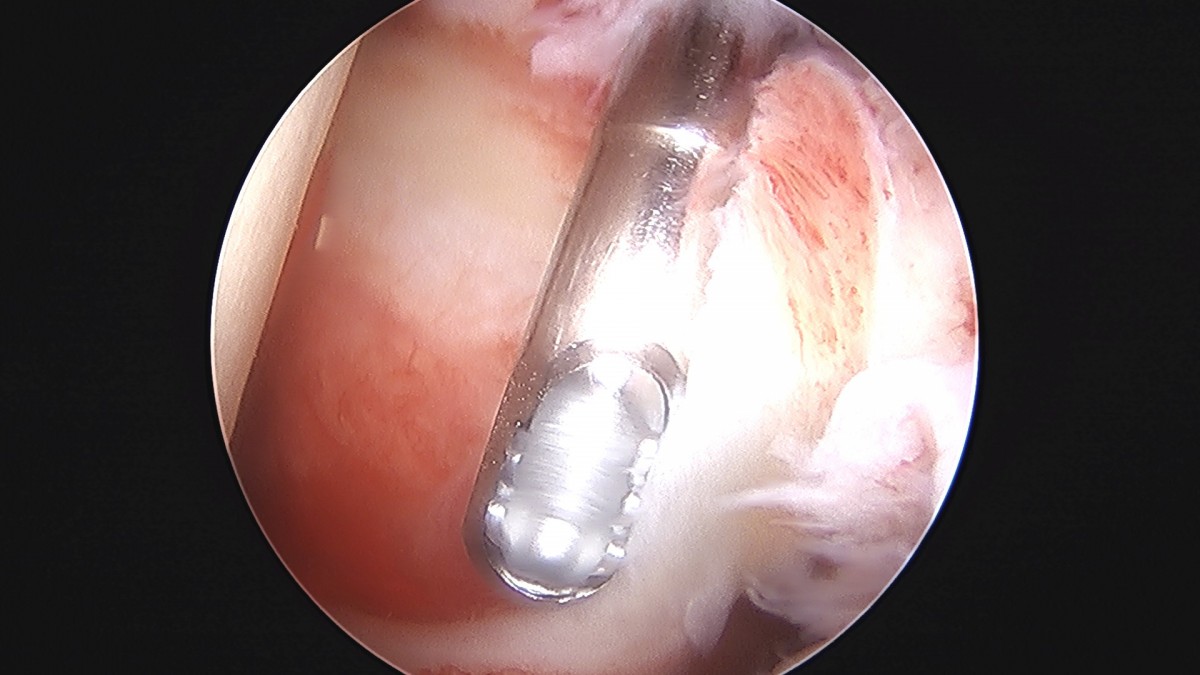

정지영원장님 어깨 관절낭 이완술 및 석회제거술 박설O 환자

작성자 최고관리자 댓글 0건 조회 732회 작성일 25-09-16 16:59